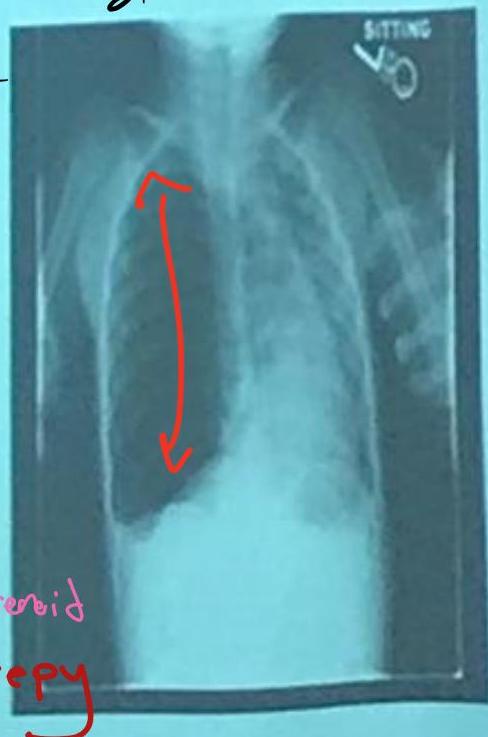

Asthma with Pneumothorax / Emphysema (CXR)

in This PIC Be Curfiat → Check Countage of the lung

Hint: Loss of contour of lung

- Check if hyperinflated

The hint is loss of Couture of lung in the emphysema → we doubt see?

Scenario: 5 year old with 3 days of acute asthma, progressive SOB, cyanosis.

CXR findings?

- Right-sided pneumothorax (or horizontal pneumothorax), subcutaneous emphysema, with left mediastinal shift

- Loss of lung opacity

- Mucous plug causing collapse/obstruction

- Other mentions in original: “Liver & mucus”, “Pneumonitis”

Examination Findings (Chest):

- Hyperresonance (increased sound on percussion)

- Pulsus paradoxus

- Decreased breath sounds

Management?

- Address the underlying cause (e.g., decompression for pneumothorax, airway clearance)

- Bronchodilator, inhaled steroid

- Suction + physiotherapy

- If pneumothorax: chest tube — 5th intercostal space, anterior axillary line

- Possible intubation